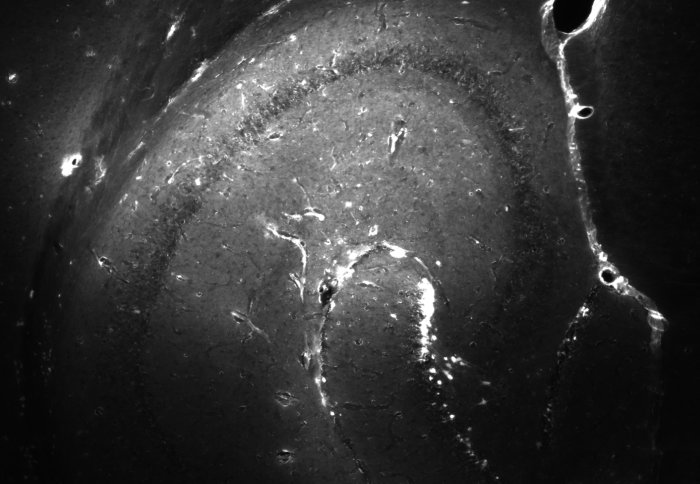

Scan of mouse brain showing even distribution of test drug via microbubbles, following short-wave ultrasound

The new technique delivered the drug more evenly throughout the brain

They found that the short-wave pulses delivered drugs evenly throughout the targeted brain areas without affecting, or damaging, surrounding tissue like the longer waves. The BBB also returned to its usual closed state within ten minutes, minimising potential damage.